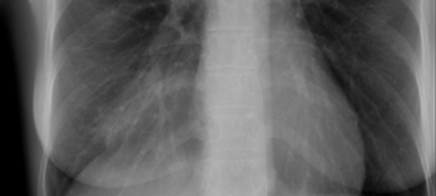

Abklärung eines chronischen Hustens:

Anamnese, Diagnostik und Therapie einer überraschenden Diagnose.